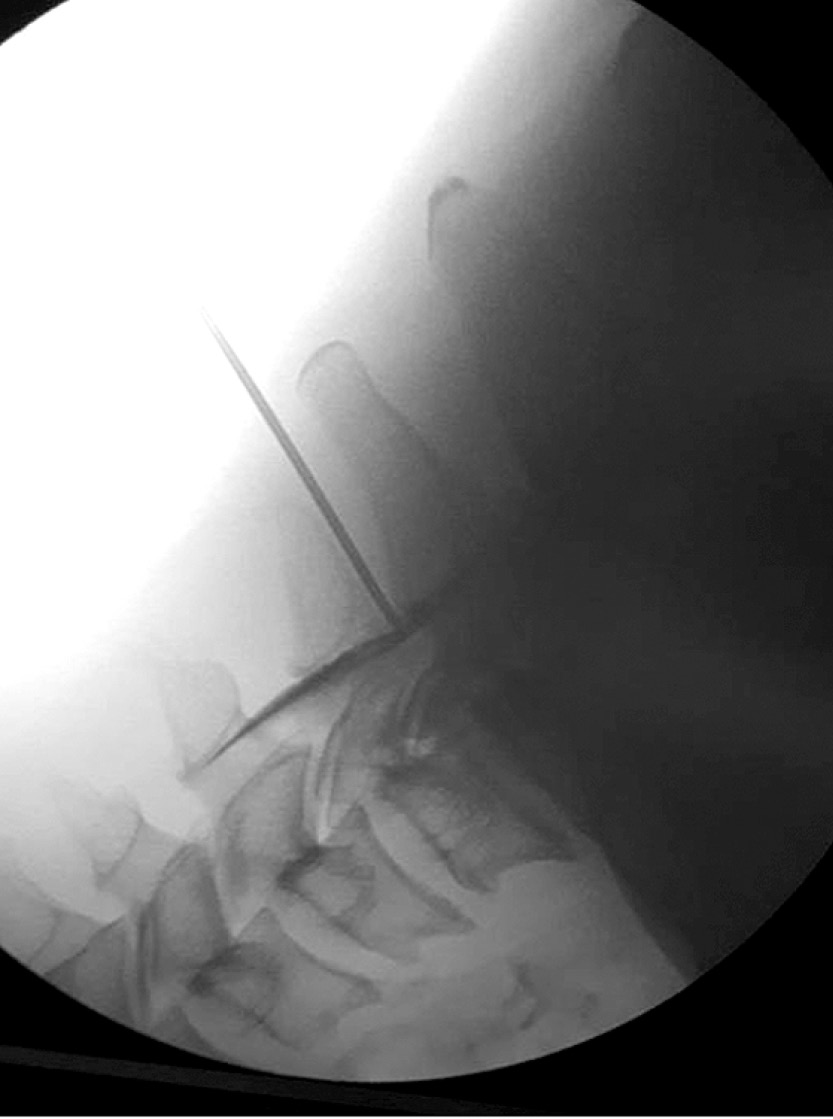

Пациент находится в положении лежа на животе с подушками под животом для уменьшения поясничного лордоза. Целевая область идентифицируется с помощью тени в виде скотч-терьера (Scotty dog shadow). Дуга флюороскопа должна быть отрегулирована и повернута на 15–30º в сторону места пункции, чтобы визуализировать тень скотч-терьера (рис. 7а), а верхний суставной отросток можно было видеть в середине межпозвонкового диска.

Рис. 7. Положение иглы при трансораминальном субпедикулярном ведении: а – в проекции 20°, b – в передне-задней проекции, c – в боковой проекции / Fig. 7. Needle position in transoraminal subpedicular control. а – in projection 20°, b – in anterior-posterior projection b – in lateral projection

После обработки операционного поля раствором антисептика игла продвигается к области inferolateral interarticularis (безопасный треугольник) для верхнего межпозвонкового отверстия. Когда кончик иглы достигает нижнелатеральной границы (угол между нижней челюстью и шеей скотч-терьера), дуга флюороскопа должна быть повернута в боковую проекцию. Иглу постепенно необходимо продвигать к передней и верхней сторонам межпозвоночного отверстия. Когда игла достигнет конечного места, должен быть проведён аспирационный тест для проверки обнаружения крови, далее вводится 1 мл йодсодержащего контрастного вещества под рентгеноскопией в режиме реального времени, чтобы определить, было ли введено вещество в переднее эпидуральное пространство.